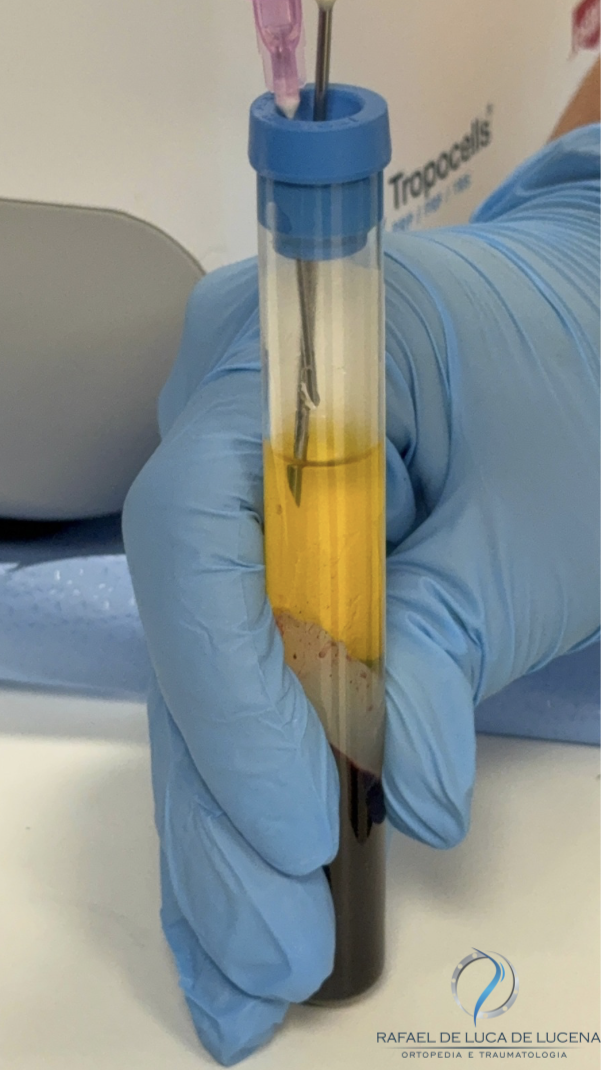

3) PRP — Plasma Rico em Plaquetas

Preparo autólogo com alta concentração de plaquetas e fatores de crescimento. Modula inflamação, favorece reparo e pode manter benefício por 6–12 meses em casos selecionados. Em alguns estudos, supera HA ou apresenta efeito semelhante com maior duração.

4) Ortobiológicos avançados (BMA e BMAC/ MSCs)

BMA (aspirado de medula óssea) e MSCs têm propriedades imunomoduladoras e de suporte ao tecido, com resultados promissores em artrose leve a moderada. A indicação segue critérios clínicos e regulamentares.